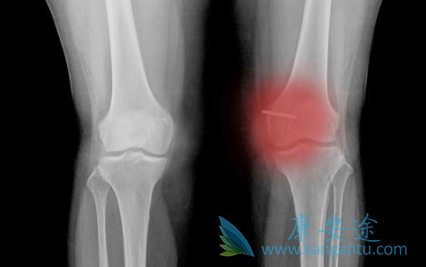

骨纤维肉瘤在骨骼发病部位,类似于骨肉瘤及恶性纤维组织细胞瘤,主要侵及长管状骨,其次为股骨、胫骨、肱骨、腓骨、桡骨、尺骨,膝关节周围骨纤维肉瘤为33%~80%,手及足部小骨少见,骨盆骨发病约为9%,颅骨如果以前无Paget病或未经过放射治疗者,发病极为罕见。